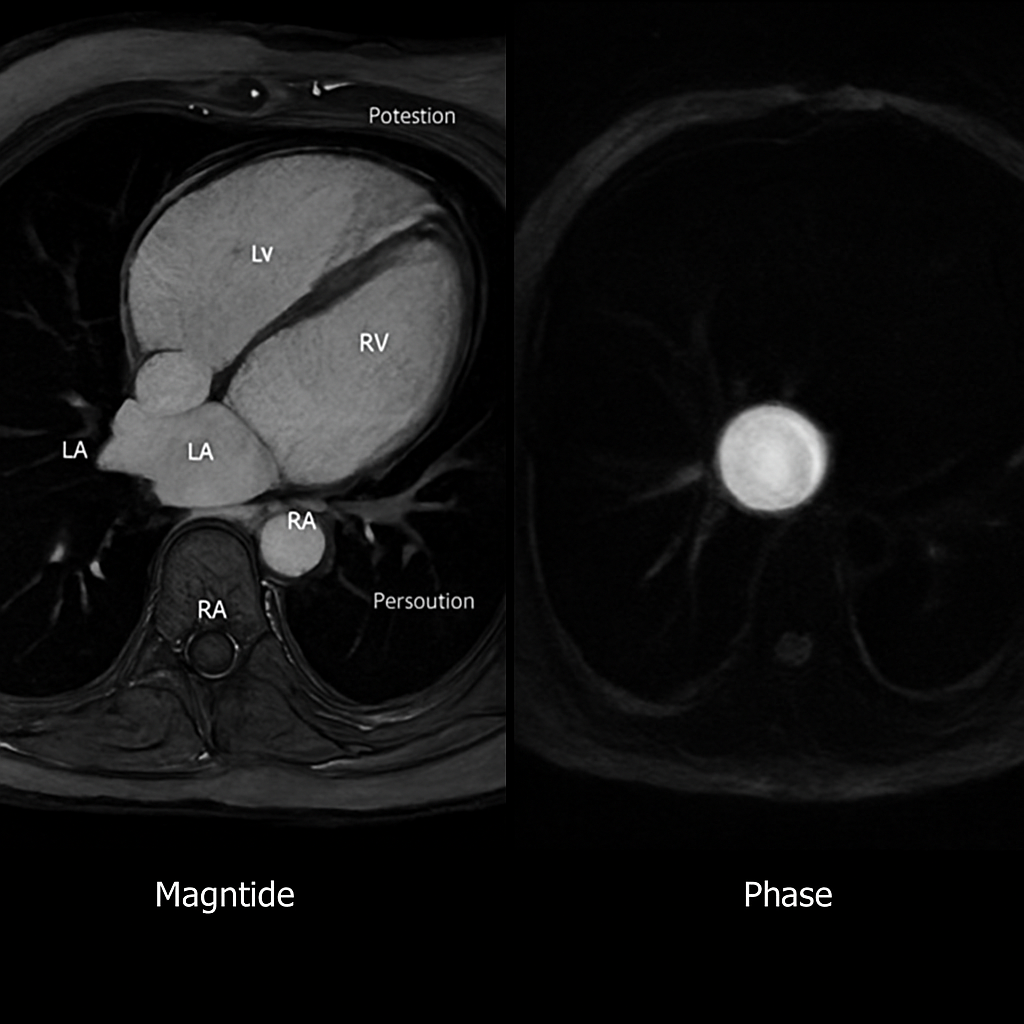

MRI — Phase-Contrast Flow (Aortic Valve)

Phase-contrast velocity-encoded MRI through the aortic valve plane showing flow measurement. Magnitude and phase images. Used for stroke volume and regurgitation assessment.

MRI AI Generated 2026-03-16

Phase Contrast Aortic

2D phase-contrast flow through aortic valve. Show magnitude image (anatomy) and velocity map (bright = forward flow).

OpenAI gpt-image-1